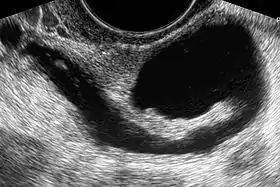

Through transvaginal sonography ovarian cysts can be aspirated. This technique is also used in transvaginal oocyte retrieval to obtain human eggs (oocytes) through sonographic directed transvaginal puncture of ovarian follicles in IVF.

Sonohysterography is a specialized procedure by which fluid, usually sterile saline (then called saline infusion sonography or SIS), is instilled into the uterine cavity, and gynecologic sonography performed at the same time. A review in 2015 came to the conclusion that SIS is highly sensitive in the detection of intrauterine abnormalities in subfertile women, comparable to hysteroscopy. SIS is highly sensitive and specific test in the diagnosis of uterine polyps, submucous uterine fibroids, uterine anomalies and intrauterine adhesions (as part of Asherman's syndrome), and can be used as a screening tool for subfertile women prior to IVF treatment.[4]